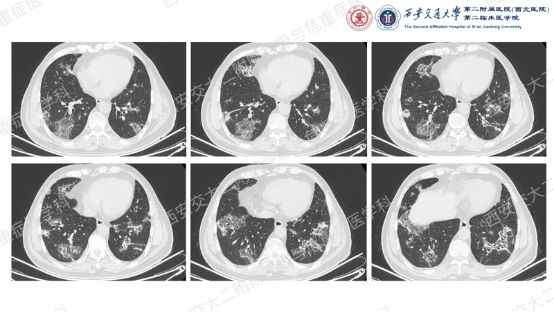

影像方寸藏玄机,同影异病辨真章。前几期我们一直在探索弥漫性囊性肺疾病的诊断,这一期我们切换到不同的影像模式,挖掘一下弥漫性肺部阴影的鉴别诊断。让我们继续乘风破浪,抽丝剥茧,解锁临床那些有意思的病例谜题吧!

结合以上病史及胸部CT,您的初步考虑?